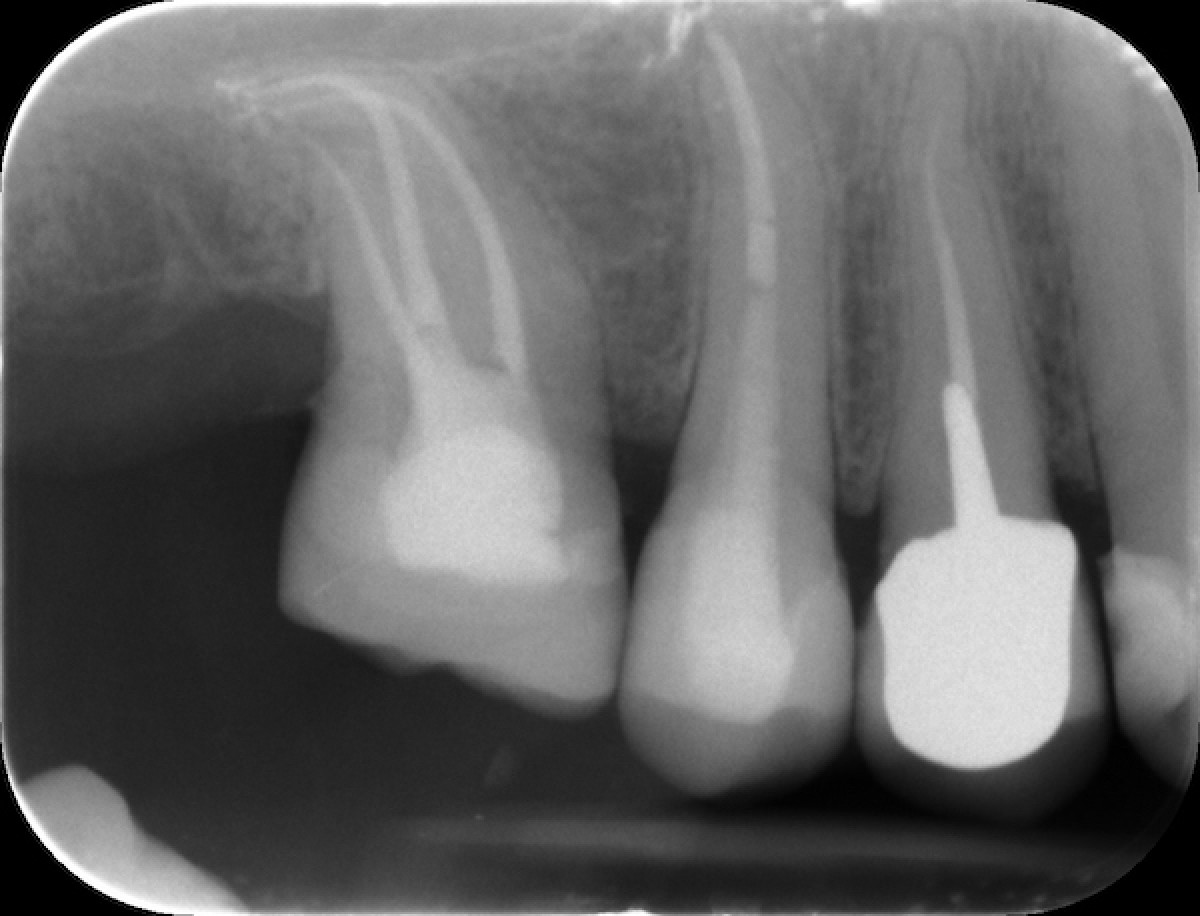

54 ys old male patient came with the complaint of pain and sensitivity in mandibular right first molar and endo-treatment was advised.

After accessing the pulp chamber and locating all the canal orifices, patency to length is confirmed with a stainless-steel manual file (0.10-0.15) and the Hyflex file sequence is selected in relation to the anatomical challenge encountered during manual scouting and the analysis of the preoperative x-ray  showed a complex and highly curved anatomy of the roots. The canal orifices were relocated using the Orifice Opener EDM In this case a 15.3 and a 20.5 were used to create a smooth mechanical glide path thanks to the great flexibility and cutting efficiency of the file. The distal canal was completed with the OneFile while in the palatal and mesio-buccal was not possible to reach WL with 25.8 EDM because of the curvature. Thus the sequence was completed with 25.4, 30.4, 35.4 from cm files sequence and 40.4 EDM file in both canals, according to the apical diameter gouging. Cold 5 % sodium hypochlorite was used throughout the procedure as the irrigant. Canals were dried with paper point and obturation was done by using single cones of taper and size corresponding to the ones of the last file used for shaping plus Gutta Flow Bioseal as cement. The tooth was restored with a composite overlay (figure 6,7).